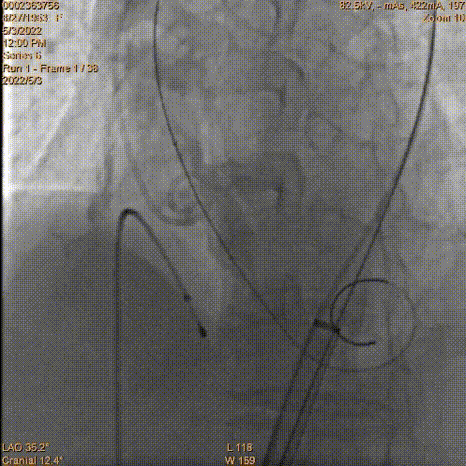

瓣膜脱钩

AV23瓣膜完全释放

术后无瓣周漏

平均压差降为9mmHg平均流速降为1.41m/s